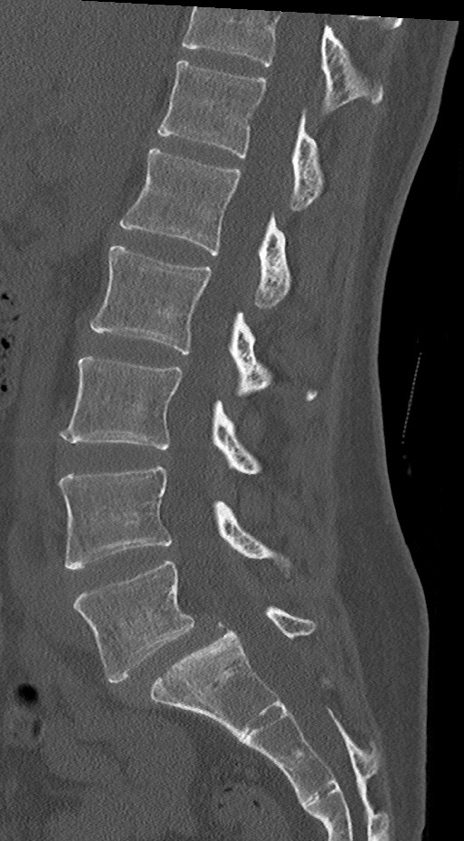

【整形】TIPS症例4 腰椎CT(矢状断像)

腰椎CT

冠状断像